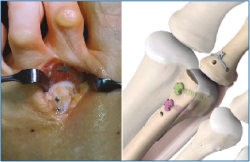

6. Retiramos el distractor y la agK de la falange, y realizamos 2 pequeños túneles de dorsal a plantar en la base de F1 con una broca o agK de 1,2 mm (Figura 10). Estos pueden disponerse cruzados o en paralelo. Aunque la disposición paralela pudiera teóricamente debilitar la base de F1 al ser prácticamente subcondrales, realizarlos cruzados tiene la desventaja de poder interferirse en el pase de las suturas. A través de estos túneles recuperamos las suturas preparadas en el extremo distal de la placa, de plantar a dorsal (Figura 11 y Vídeo).

Figura 10. Doble tunelización en base de F1.

Figura 11. Recuperación de las suturas de plantar a dorsal, a través de los túneles de F1.